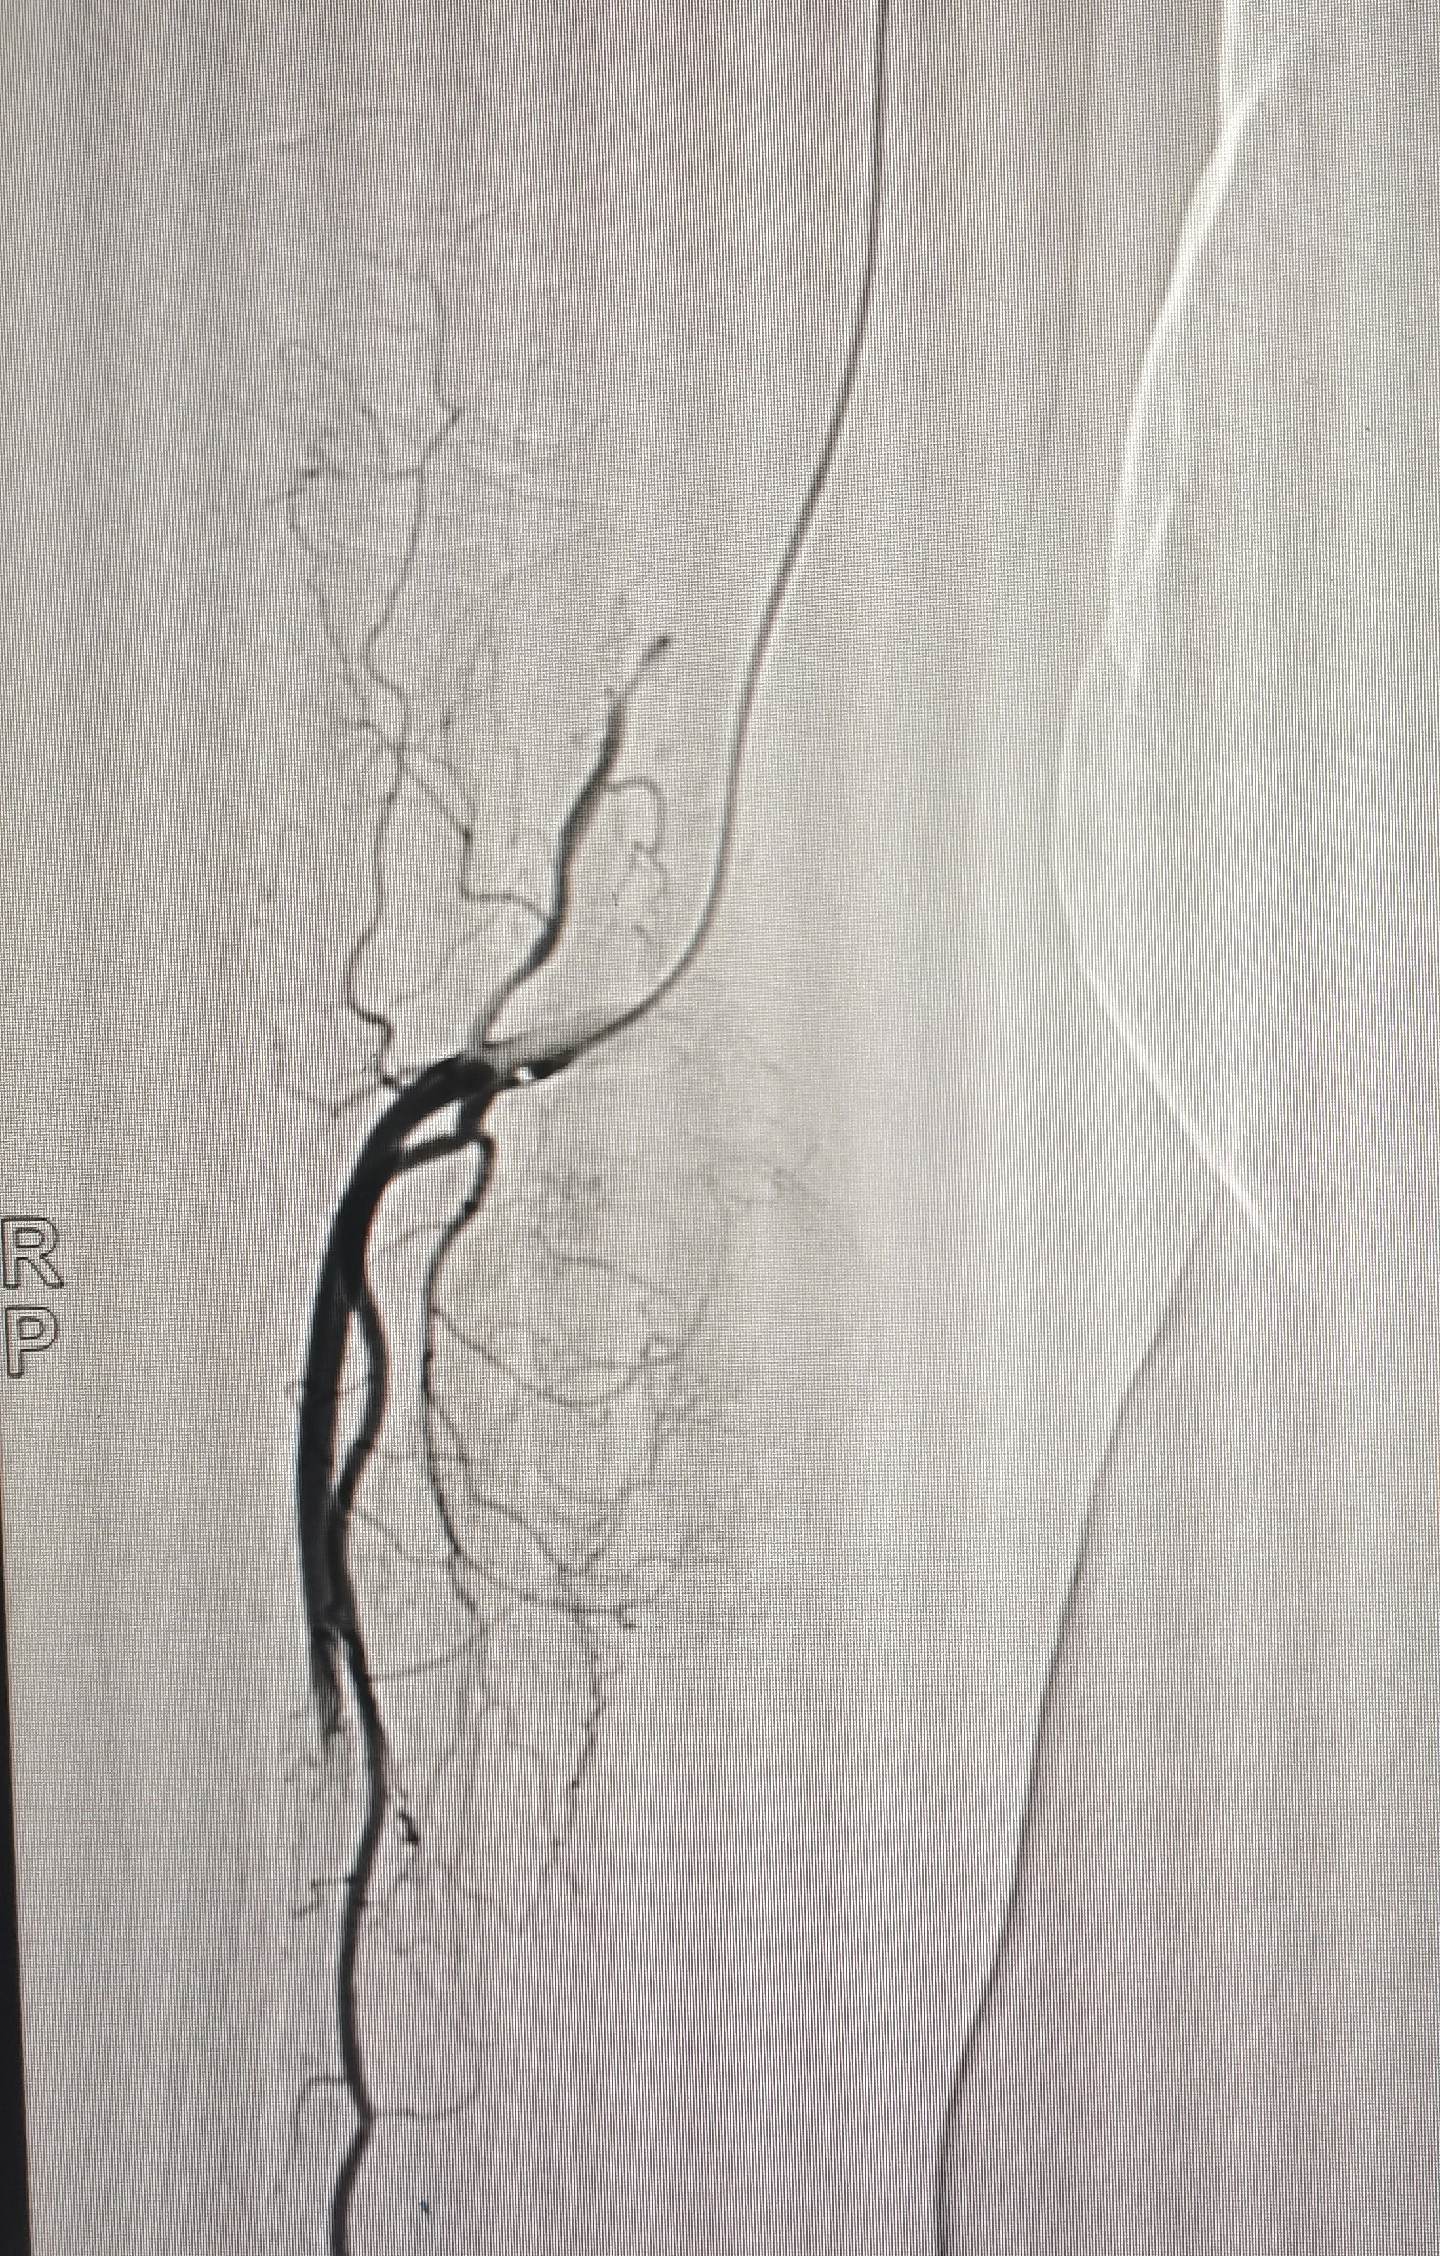

今日病例:老年右前臂纤维肉瘤行4次手术切